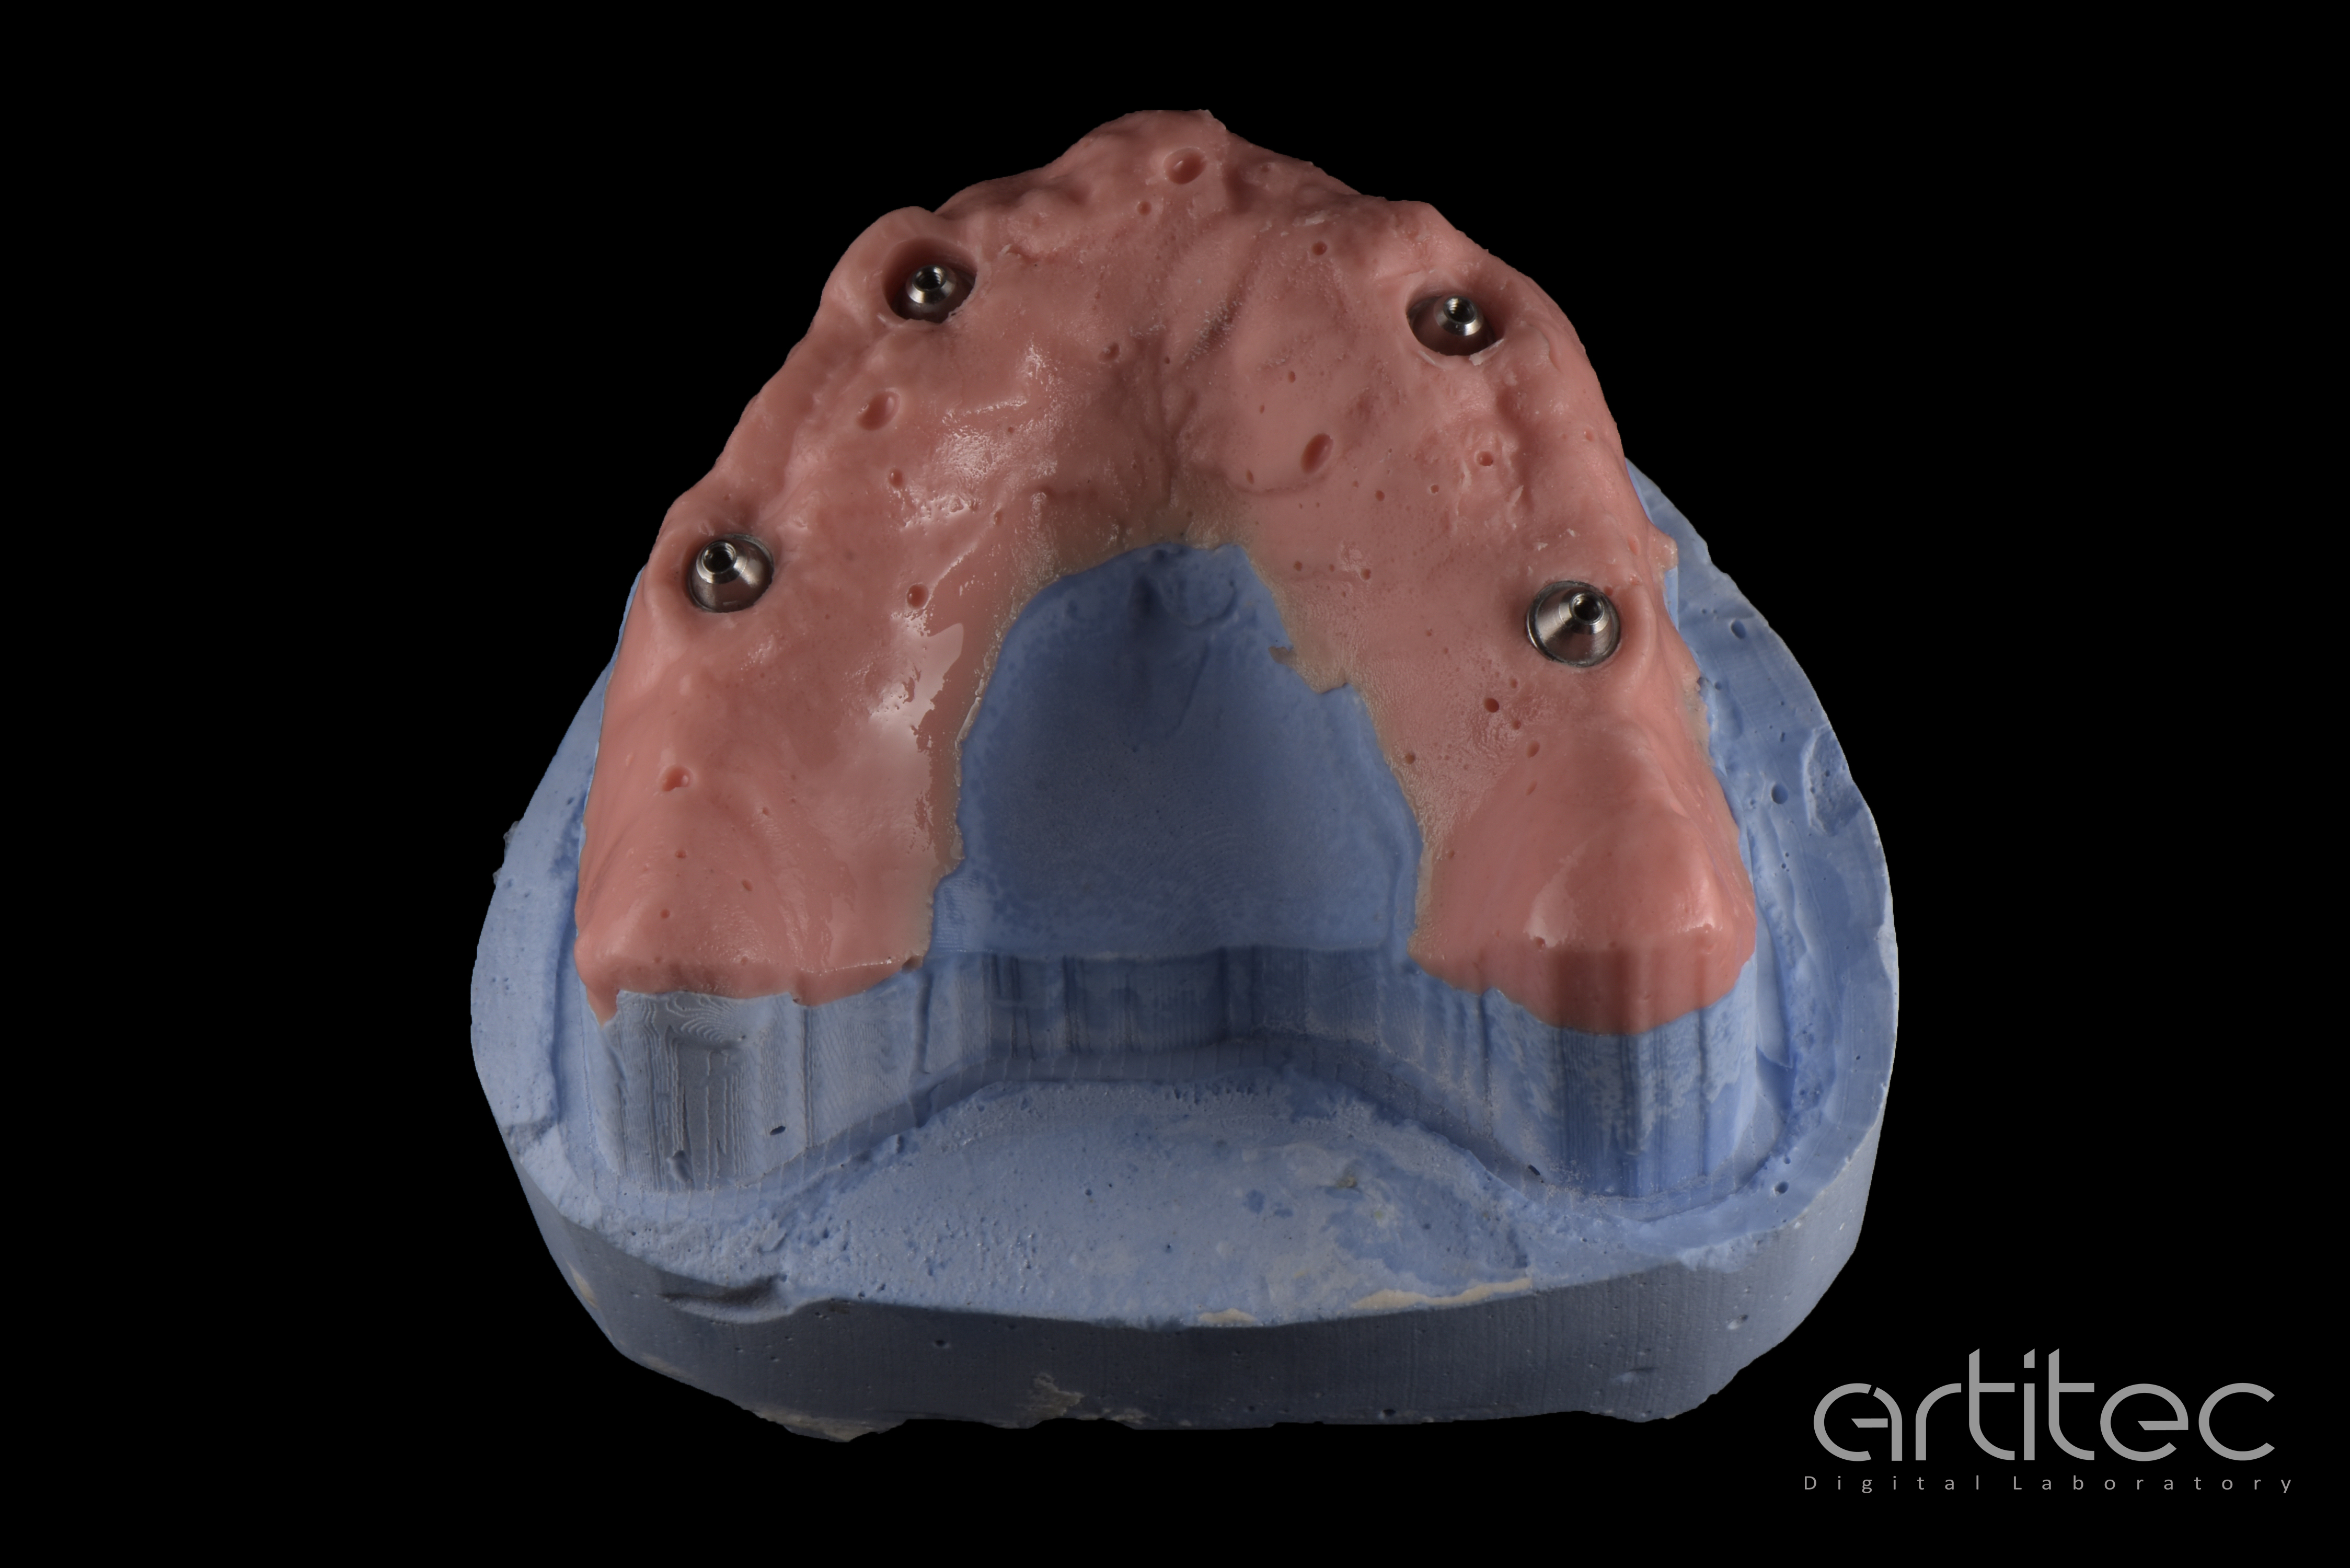

Fig. 18 Realizzazione del modello ibrido

Fig. 19 Provino da stampa 3D del progetto definitivo

Fig. 20 Vista occlusale del provino da stampa 3D del progetto definitivo

Fig. 21 Vista basale con inserimento dei linker

Fig. 22 Controllo e test di avvitamento su modello ibrido